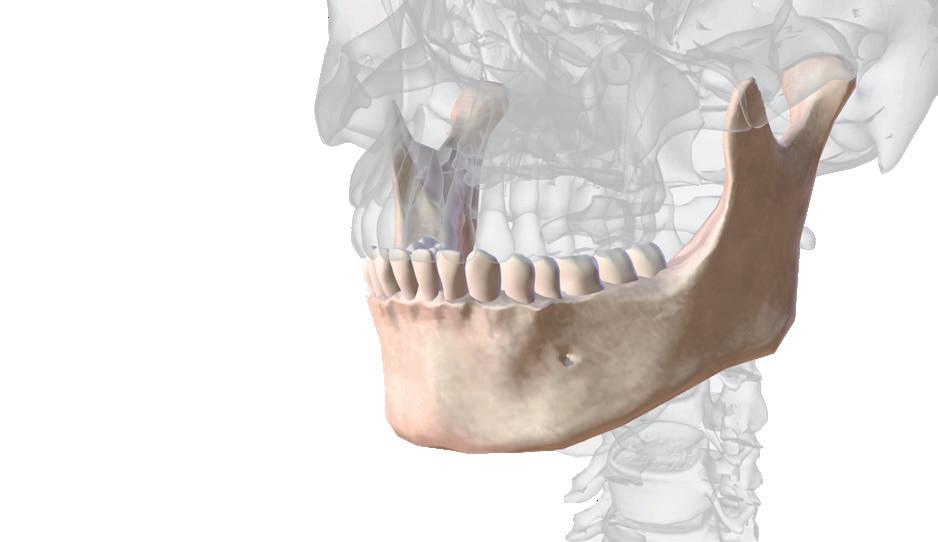

Ein starkes Fundament

Ein gesunder Kiefer ist entscheidend für den sicheren Halt von Implantaten. Doch was passiert, wenn Knochen fehlt? Dr. Levente Losonczy ist Experte auf diesem Gebiet. Er erklärt, wie ein Kieferknochenaufbau funktioniert, warum er oft unverzichtbar ist und welche modernen Techniken den Eingriff heute deutlich schonender und schneller machen. Der Zahnarzt gibt außerdem wertvolle Tipps zur Nachsorge.

Herr Dr. Losonczy, was versteht man unter einem Kieferknochenaufbau, und wann ist er notwendig? Dabei handelt es sich um einen kleinen chirurgischen Eingriff, bei dem fehlende Knochensubstanz im Kiefer ersetzt wird. Damit wird wieder eine stabile Grundlage geschaffen, meistens für Zahnimplantate, manchmal auch zur Behandlung von

Schäden nach einem Unfall oder nach bakteriellen Entzündungen im Mundraum, die zu einem Knochenschwund führen. Ein solcher Aufbau ist dann notwendig, wenn nicht mehr ausreichend natürliche Knochensubstanz vorhanden ist, um dem Zahnersatz genügend Halt zu geben.

Wenn nicht ausreichend natürliche Knochensubstanz vorhanden ist, um einem Implantat Halt zu geben, muss der Kieferknochen aufgebaut werden.

Kieferknochenaufbau

Manchmal reicht der eigene Kieferknochen nicht mehr aus, um einen festen Halt für Zahnersatz oder Implantate zu bieten. Gründe dafür können Zahnentfernungen, Entzündungen oder einfach der natürliche Knochenabbau im Laufe der Jahre sein. In solchen Fällen kann ein Kieferknochenaufbau helfen. Dabei wird fehlender Knochen ersetzt oder neu aufgebaut, damit wieder eine stabile Grundlage entsteht. Für den Aufbau gibt es verschiedene chirurgische Möglichkeiten.

Was führt dazu, dass Kieferknochen verloren geht? Kieferknochen kann aus verschiedenen Gründen verloren gehen. Am häufigsten passiert das nach einem Zahnverlust, weil der Knochen an dieser Stelle nicht mehr belastet wird und sich mit der Zeit zurückbildet. Je länger der Zahn fehlt, desto stärker kann dieser Knochenschwund sein. Auch bestimmte Erkrankungen und Behandlungen können den Knochenabbau beschleunigen, zum Beispiel eine chronische Parodontitis, Chemotherapie oder Bestrahlungen im Kopf- und Halsbereich. Ebenso kann eine schwere Nierenerkrankung die Knochenqualität beeinträchtigen. Rauchen wirkt sich ebenfalls negativ aus, da es die Durchblutung und Heilung im Kiefer behindert.